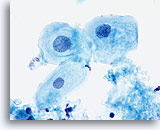

The ThinPrep Pap Test® minimizes the troublesome artifacts inherent in smear and spray fixation. This allows for

the nucleus to be adequately visualized facilitating a more definitive diagnosis. The epithelial cells that are generally incorporated in the ASC category are the mature squamous and squamous metaplastic cells exhibiting changes that are minimal and fall short of a diagnosis of LSIL or HSIL. The nuclei are slightly enlarged and this enlargement is compared to the normal entity of the same cell type. The nuclei may show slight nuclear membrane irregularities but are more often smooth. When dealing with the metaplastic component, one needs to make sure that the irregularities aren’t due to a vacuole(s) pushing the nucleus into the aberrant shape. The chromatin pattern is finely granular and evenly distributed. Chromocenters or nucleoli are generally inconspicuous or absent unless a reactive process is occurring in conjunction with the atypia at which point the differential diagnosis of reactive needs to be considered depending upon the presence or lack of the other criteria.

With either conventional or ThinPrep® slides, an ASC interpretation may arise from any of several different cellular changes, including but not limited to, squamous atypia, atypical squamous metaplasia, and atypical parakeratosis. The criteria for ASC on the ThinPrep Pap Test are as follows:

The images that follow are ThinPrep® Pap Test specimens that reasonably could be interpreted as reactive changes,

ASC-US, and LSIL.